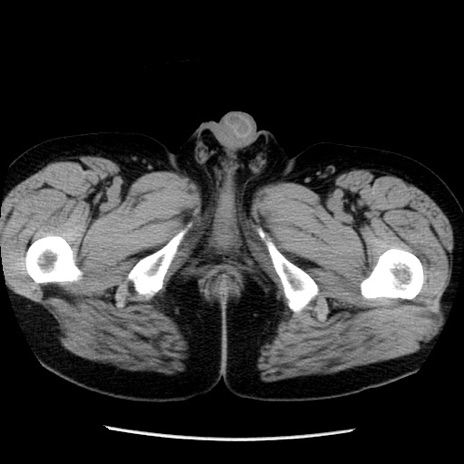

症例29(横断像)

【症例】40歳代男性

【現病歴】2日前から胃痛あり。徐々に周期的な激痛に変化した。本日になっても激痛があるため受診。

【身体所見】意識清明、BT 38-39℃台あり、腹部:膨満、やや硬、右下腹部に圧痛あり。

【データ】WBC 8500、CRP 23.26